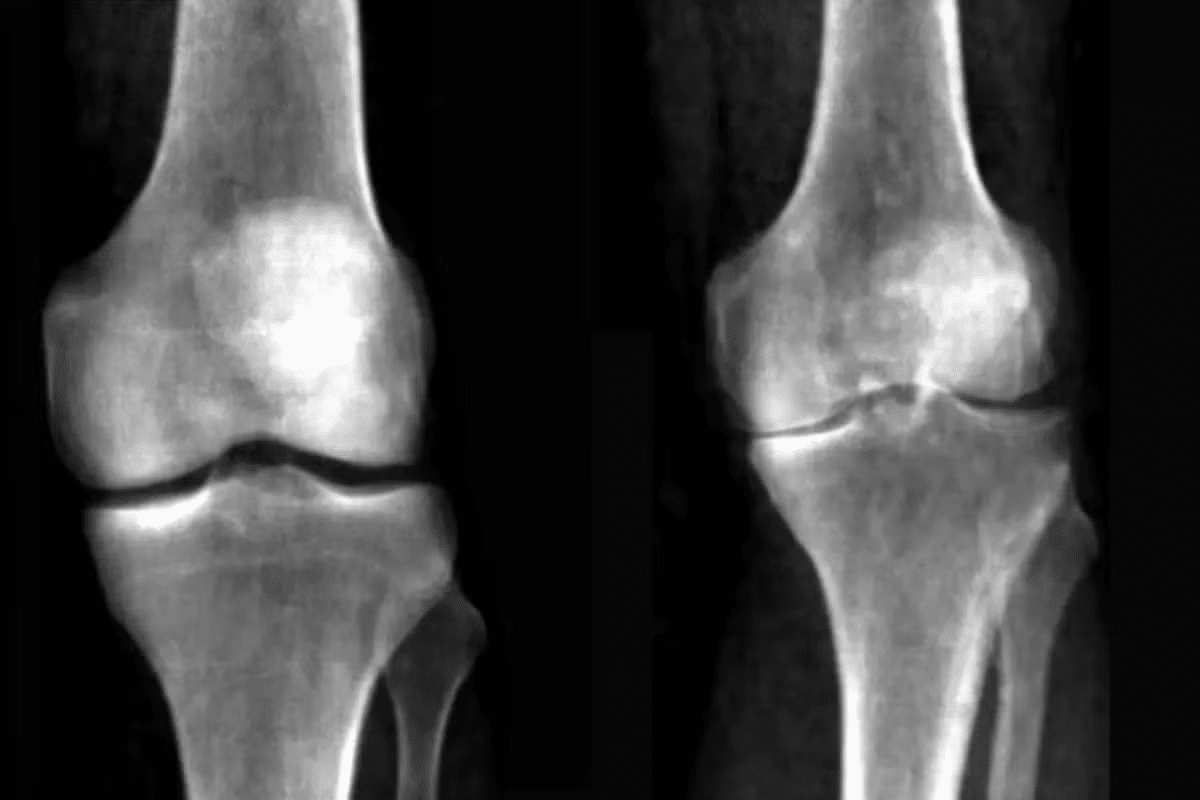

Osteoarthritis Flare Characteristics

Osteoarthritis (OA) is the most common arthritis, affecting joints like hips, knees, and hands. OA flares are often caused by overuse or repetitive strain. This leads to more pain and stiffness in the affected joints.